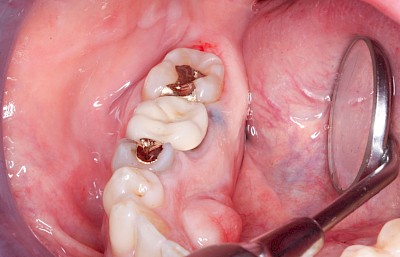

Häufig zu beobachten sind einzelne dunkle Flecken im Nahbereich der Zähne. Häufig handelt es sich dabei um Amalgam- oder Metall-Tätowierungen. Bei zahnärztlichen Behandlungen kann es zur "Versprengung" von Metall-Anteilen von Füllungen oder Kronen kommen. Diese lagern sich dann reizlos in die Schleimhaut ein.

Beispiele 10 Bilder